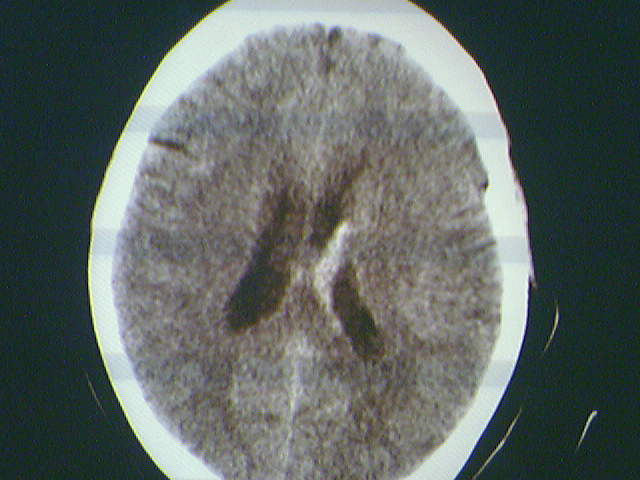

标题: CT13117:外伤后昏迷 [打印本页]

标题: CT13117:外伤后昏迷

左侧侧脑室室管膜下出血.

考虑脑室系统出血,建议上传完整图像

脑室内出血

左侧侧脑室室管膜下出血.  支持!zhuyi注意排除弥漫性轴索损伤。